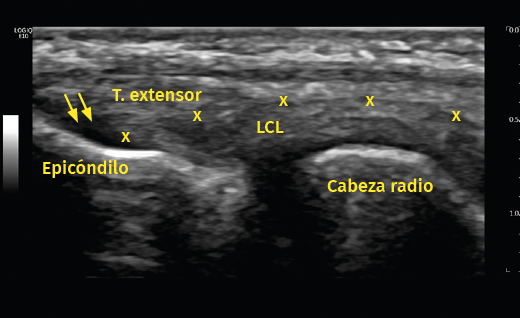

Otro método utilizado es la ecografía, que permite detectar cambios estructurales que afectan a los tendones (engrosamiento, adelgazamiento, áreas degenerativas intrasustancia y desgarros del tendón, por ejemplo), irregularidades óseas o depósitos de calcio(6)(Figura 6). Además, la exploración con Doppler color permite valorar la presencia de neovascularización (Figura 7). La ausencia de este hallazgo o de cambios en la estructura del tendón en las pruebas de imagen debe hacer dudar sobre el diagnóstico de tendinopatía lateral del codo(15). Tiene la ventaja de poder relacionar los síntomas del paciente con los hallazgos ecográficos en tiempo real pero, por otro lado, es operador-dependiente(12). Los estudios demuestran que esta prueba presenta una alta sensibilidad (72-88%), pero una baja especificidad (36-48,5%)(16).

Figura 6. En este examen longitudinal del tendón extensor común (T. extensor), se describen los signos ecográficos de una epicondilopatía: el aumento de grosor del tendón y la pérdida de su patrón fibrilar con áreas de pequeña rotura en su interior (flechas). Imagen cedida por el Dr. Fernando Jiménez Díaz.